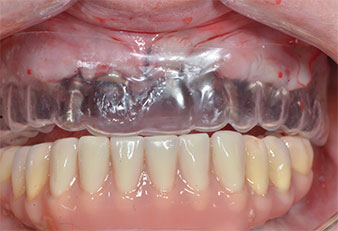

Trois ans après, le moment était venu pour elle de se doter d’une prothèse maxillaire du même type. Sur la base de la planification CBCT, l’élévation sinusale a été évitée grâce à la pose d'implants courts, et un gabarit chirurgical a été utilisé pour transférer les positions planifiées sur la crête alvéolaire (Figures 1 et 2).

Compte tenu de la dureté relative de l’os (D2) à cet endroit, les sites recevant des implants de 10mm de long aux régions 11 et 21 ont été finalisés à l'aide d’une fraise de 4mm de diamètre, associée à un contre-angle chirurgical W&H WS-75 L, au moteur d'implantologie Implantmed de W&H ainsi qu’au module Osstell ISQ de W&H. En revanche, en raison de leur structure osseuse molle, les sites postérieurs ont été préparés en vue de l’obtention d’un diamètre final de 3mm à l'aide de l’insert Piezomed I3P. Les implants ont enfin été posés par voie transgingivale (Flap Less) pour obtenir l’ostéointégration dans un délai de trois mois (Figures 6-10). L'appareil existant a été maintenu sur quatre implants provisoires (Fig. 8).